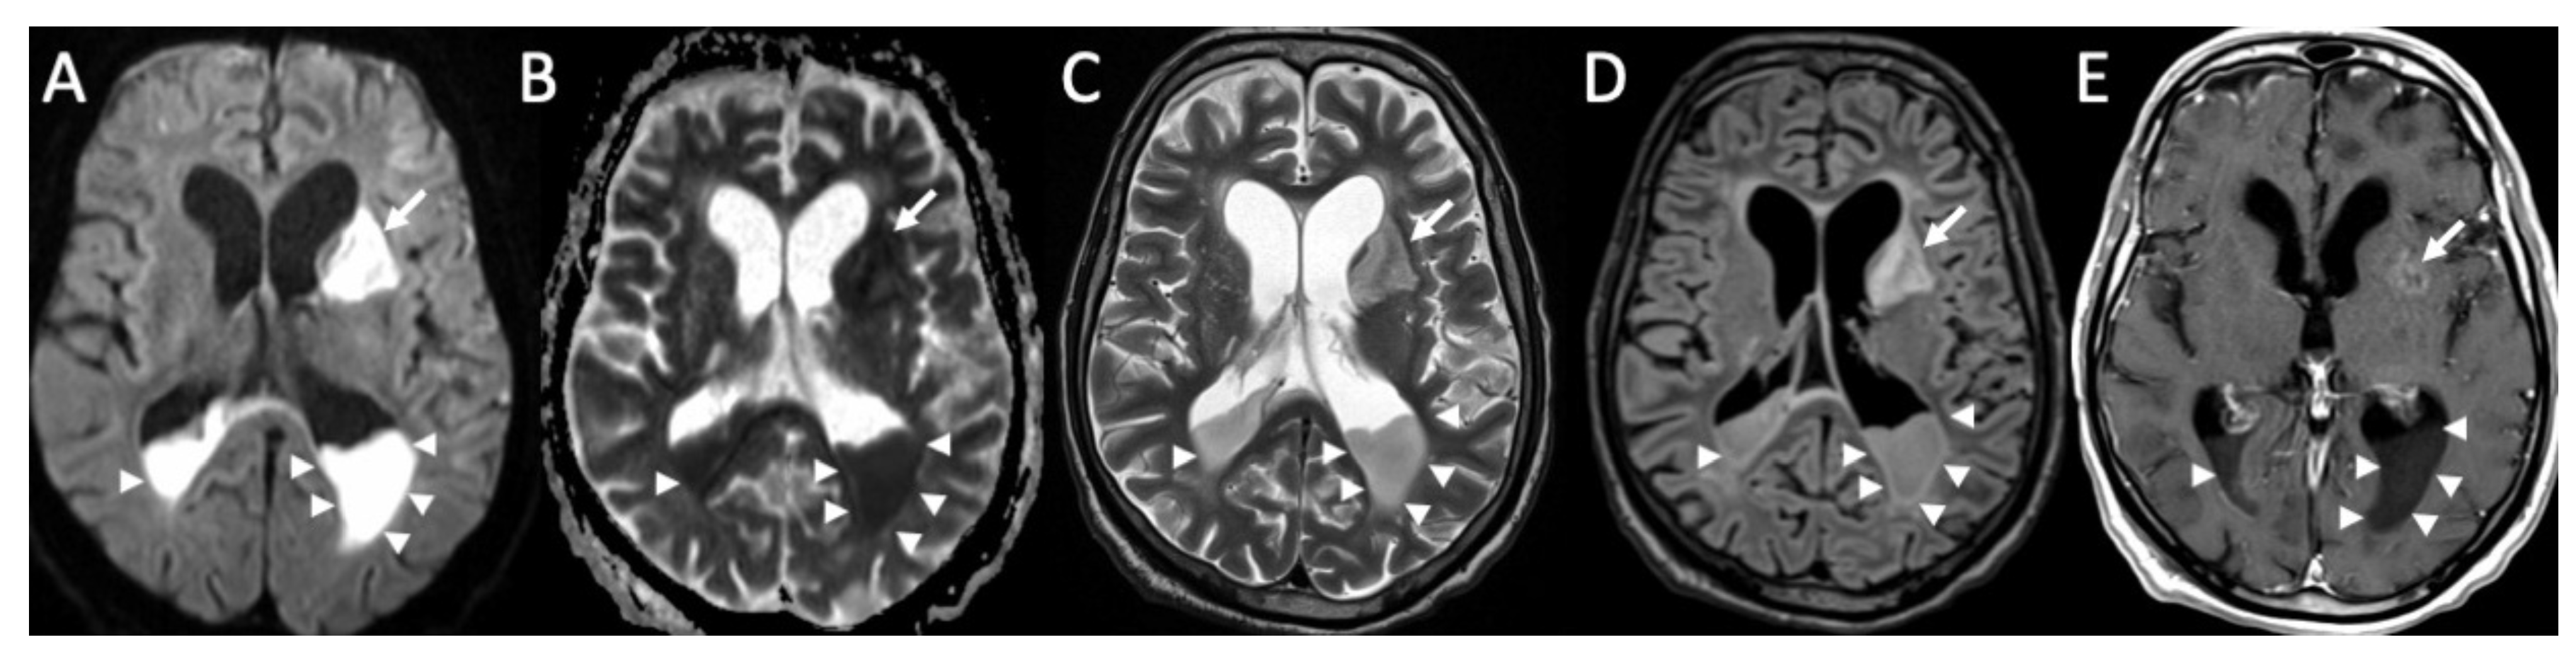

| Cryptococcus Neoformans | • Leptomeningeal enhancement • Cryptococcoma • Gelatinous pseudocysts |

| Candida albicans | • Microabscesses • Vascular lesions |

| Aspergillus fumigatus | • Abscesses • Vascular lesions |

4. Fungal Meningitis